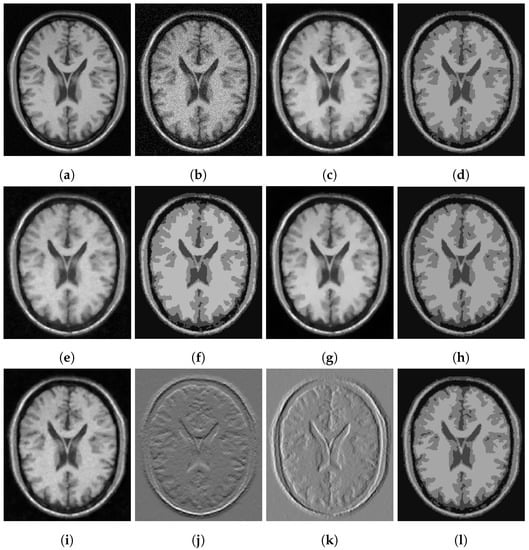

Figure 5.

MRI segmentation: (a) Clean image. (b) Noisy image used as input to the models. (c) Output of CCZ. (d) CCZ after thresholding. (e) Output of CNC. (f) CNC after thresholding. (g) Output of T-ROF. (h) T-ROF after thresholding. (i) Output g of our model. (j) Output of our model. (k) Output of our model. (l) Ours after thresholding.